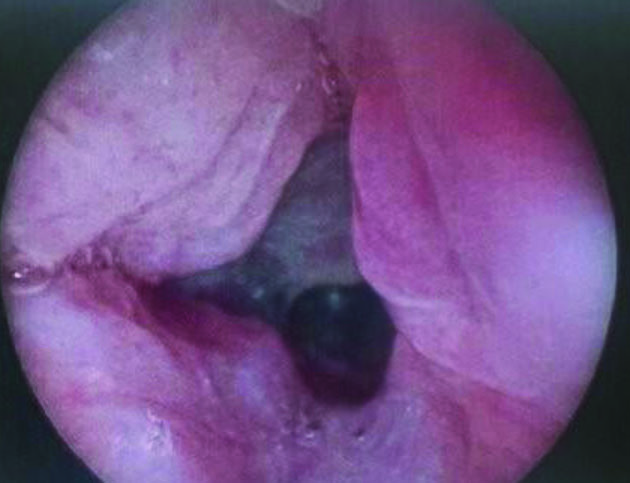

Figure 5. Subsequent bronchoscopy in the OR showing widely patent glottic and subglottic airway without granulation tissue or recurrent stenosis. Note that the posterior cartilage graft is completely covered and mucosalized by the trachealis flap.

Figure 6. Glottis and subglottis are still widely patent six months after decannulation.